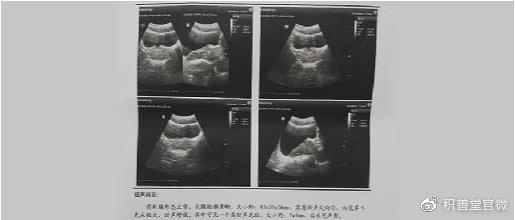

患者田某2020年7月来到西安积善堂门诊检查。

田某28岁,腺体既有器质性病变,又有功能下降。前列腺大小为:43*35*26mm,比正常尺寸明显增大;

实质回声欠均匀,内见多个光点粗大,回声增强,说明他的腺体局部出现了慢性病变,已经形成了纤维化病灶,并导致腺体局部的弹性变硬;

其中可见一个高回声光斑,约7*4mm,后不见声影,这就是腺体上的钙化病灶,这个钙化灶已经很大,可以确诊田某患的是前列腺增生伴钙化、纤维化,慢性前列腺炎。